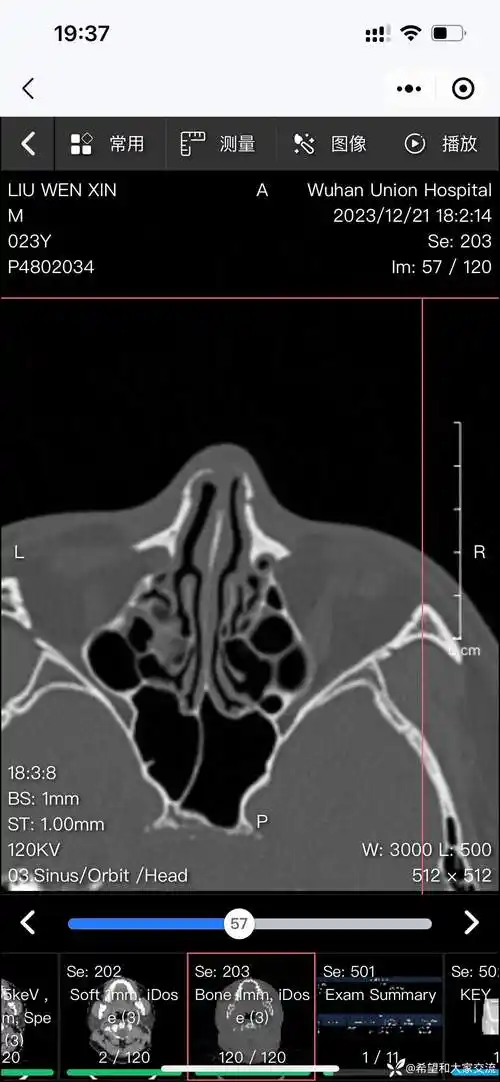

谁来帮忙看下我这张鼻部ct片

这个鼻骨是正常的吗

鼻窦炎鼻中隔偏曲有会看ct的姐妹吗

请帮忙看一下鼻部ct!